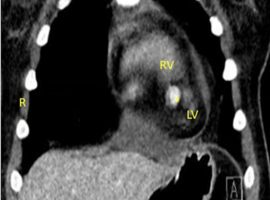

Clinical Cardiology Case Report

The Journal offers case reports in clinical cardiology, images, case series and heart surgery videos to publish. original research, research articles, review articles, case studies, commentaries, short communication, and Letters to the heart problem, heart and blood vessel disorders, cardiovascular diseases, myocardial infarction (heart attack), issues of cardiac arrest, stroke, techniques and procedure used in stent implantation, anticoagulant drugs (blood thinners), basic research in heart structure and functions and other medical conditions and associated treatments is aiming to stand out and publish remarkable findings in the major areas of cardiovascular medicine emphasizing on diagnostic, therapeutic and disease management sections.